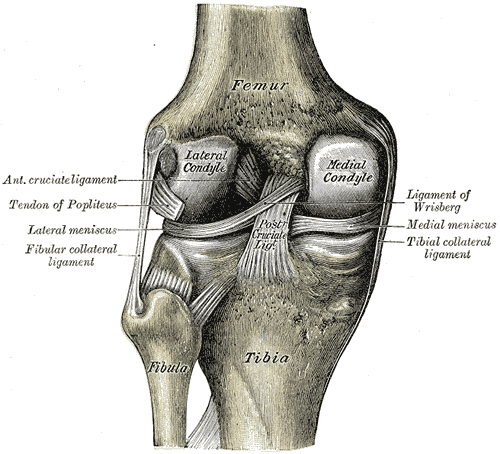

무릎 관절은 넙다리뼈, 정강이뼈, 무릎뼈의 세 뼈로 구성된다. 이 뼈들은 인대에 의해 연결되어 관절을 안정적으로 유지한다. 무릎에는 측부 인대와 십자 인대의 두 가지 유형이 있다.[1]

측부 인대는 내측 측부 인대(무릎 안쪽)와 비골 측부 인대(무릎 바깥쪽)가 있다. 이 두 인대는 무릎의 측면 움직임을 제한한다.[1]

십자 인대는 무릎 관절 안쪽에서 "X"자 모양을 형성하며, 전방 십자 인대는 정강이뼈 앞쪽에서 넙다리뼈 뒤쪽으로, 후방 십자 인대는 정강이뼈 뒤쪽에서 넙다리뼈 앞쪽으로 뻗어 있다. 전방 십자 인대는 정강이뼈가 넙다리뼈 앞으로 미끄러지는 것을 방지하고 회전 안정성을 제공한다.[1]

무릎 관절의 정강이뼈 위에는 내측 반월상 연골과 외측 반월상 연골이라 불리는 C자형 연골 구조물 두 개가 있어 뼈의 쿠션 역할을 한다.[2]